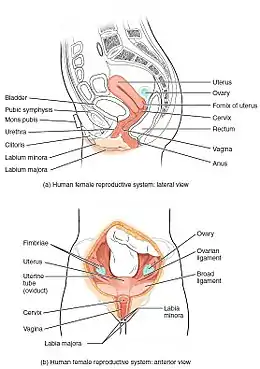

The uterus (from Latin "uterus", plural uteri) or womb (/wuːm/) is the main female hormone-responsive, secondary sex organ of the reproductive system in humans and most other mammals. Things occurring in the uterus are described with the term in utero. In the human, the lower end of the uterus, the cervix, opens into the vagina, while the upper end, the fundus, is connected to the fallopian tubes. It is within the uterus that the fetus develops during gestation. In the human embryo, the uterus develops from the paramesonephric ducts which fuse into the single organ known as a simplex uterus. The uterus has different forms in many other animals and in some it exists as two separate uteri known as a duplex uterus.

Structure

The uterus is located within the pelvic region immediately behind and almost overlying the bladder, and in front of the sigmoid colon. The human uterus is pear-shaped and about 7.6 cm (3.0 in) long, 4.5 cm (1.8 in) broad (side to side), and 3.0 cm (1.2 in) thick.[1][2] A typical adult uterus weighs about 60 grams. The uterus can be divided anatomically into four regions: the fundus – the uppermost rounded portion of the uterus, the corpus (body), the cervix, and the cervical canal. The cervix protrudes into the vagina. The uterus is held in position within the pelvis by ligaments, which are part of the endopelvic fascia. These ligaments include the pubocervical ligaments, the cardinal ligaments, and the uterosacral ligaments. It is covered by a sheet-like fold of peritoneum, the broad ligament.[3]

From outside to inside, regions of the uterus include:

- Cervix uteri – "neck of uterus"

- External orifice of the uterus

- Cervical canal

- Internal orifice of the uterus

- Body (Latin: Corpus)

- Uterine cavity

- Fundus